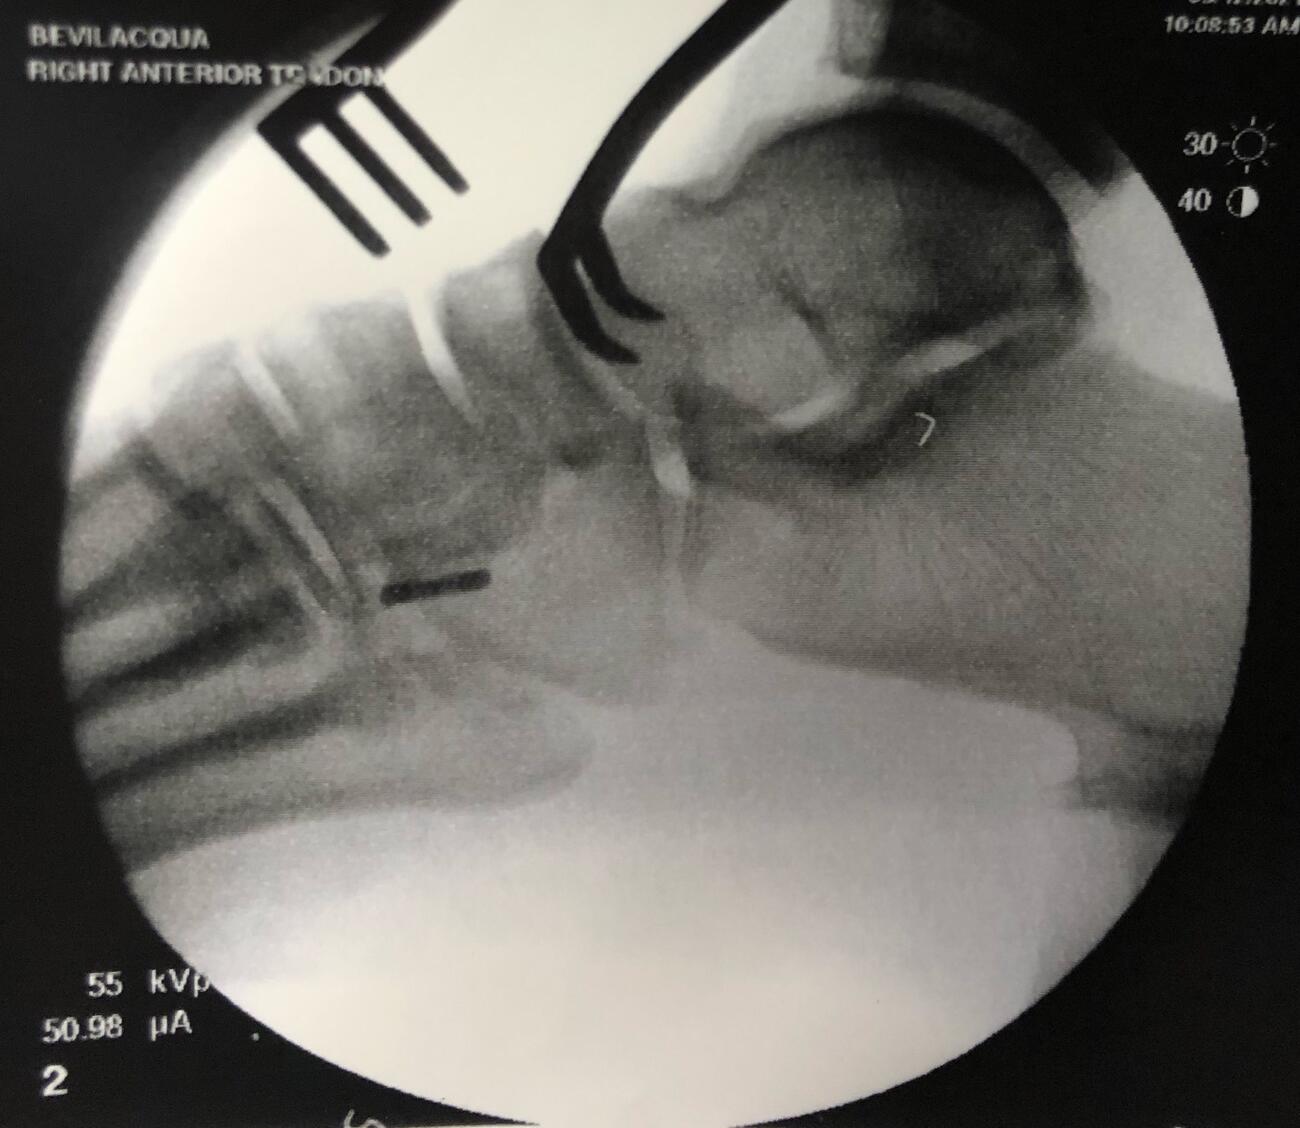

Next, the surgeon identifies the dorsal aspect of the medial cuneiform and centralizes a guide wire on the bone using intraoperative fluoroscopy. The guide wire placement is perpendicular to the dorsal cortex and advanced bicortically. One directly visualizes and confirms via fluoroscopy the position and orientation of the guide pin, exercising caution to prevent penetrating the proximal or distal joints.

Drilling of an appropriately sized bone tunnel then takes place over the guide wire in the medial cuneiform from dorsal to plantar, being careful not to penetrate the plantar cortex. One then threads the suture limbs (from the previously placed whip stitch) through the cortical button, and the button inserter advances the button through the medial cuneiform from dorsal to plantar. Fluoroscopy confirms the button has flipped and is in proper position, sitting flush against the plantar cortex (see fifth and sixth photos above). The tendon is then carefully brought into the tunnel and advanced by pulling the sutures with controlled tension. Once the tendon is in satisfactory position, with the appropriate tension, insertion of a tenodesis screw further secures the tendon in place.